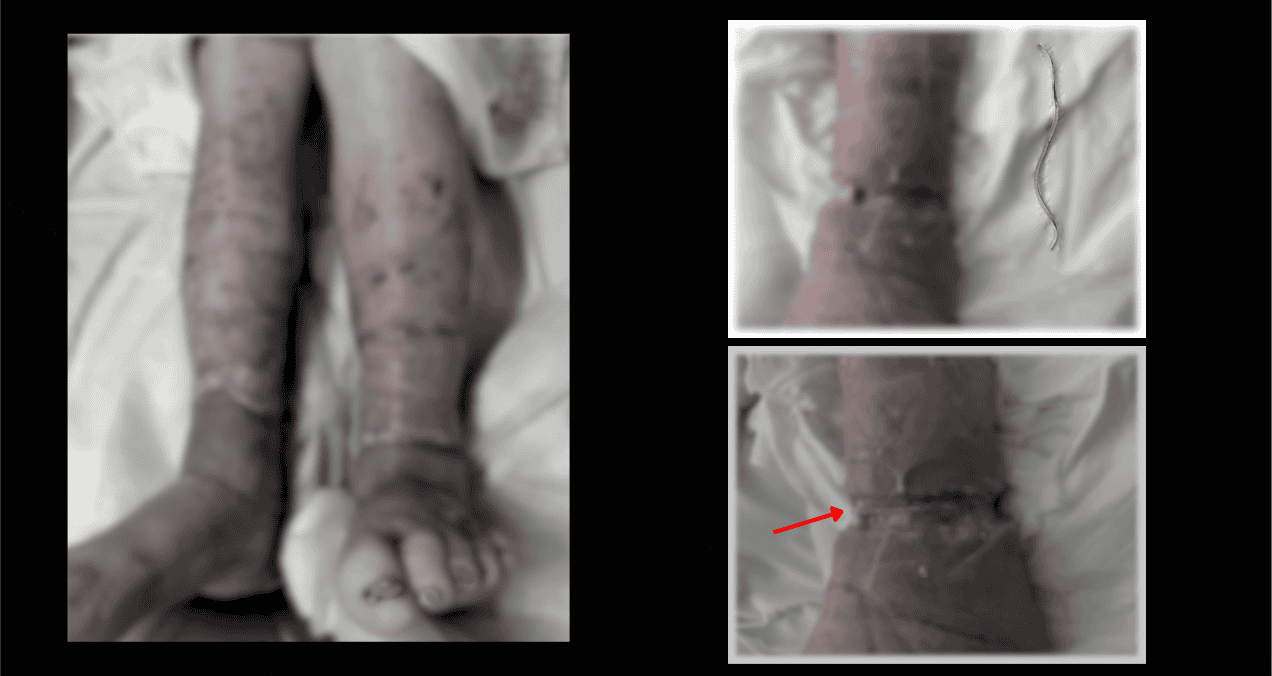

El diagnóstico ocurrió durante el desbridamiento quirúrgico realizado en planta. Tras eliminar meticulosamente el tejido necrótico y el esfacelo, se visualizó una estructura lineal, delgada y de color canela que circundaba completamente la extremidad y se encontraba incrustada en la fascia.

Identificada como una banda elástica de goma, fue seccionada y extraída inmediatamente. La herida mostró entonces un lecho viable aunque profundamente afectado. Pese a este hallazgo, el paciente continuaba sin poder explicar el origen o motivo de la colocación de la banda.